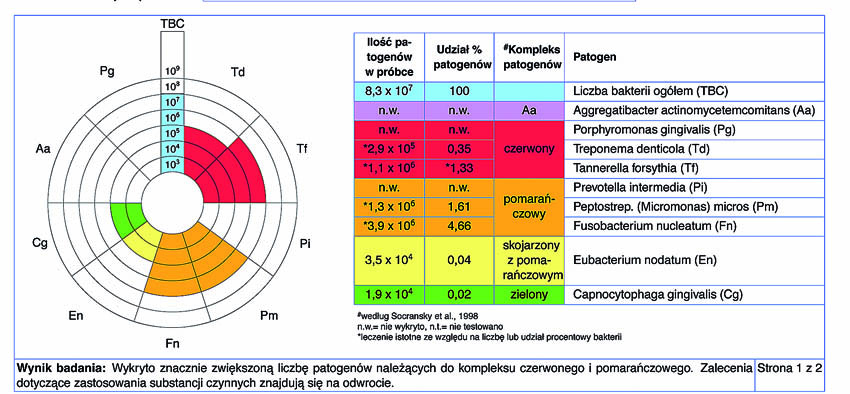

Στην περίπτωση που υπάρχει μία σημαντικά βαρεία νόσος, μεγάλη κινητικότητα των δοντιών και πολλά ελλείποντα δόντια, συνιστάται να διεξάγονται μοριακές-βιολογικές εξετάσεις για να πραγματοποιείται μία ποσοτική αξιολόγηση των περιοπαθογόνων.

Πριν τη θεραπεία, η ασθενής υποβλήθηκε σε διαδικασία υποουλικού καθαρισμού με ξέστρα υπερήχων. Μετά τον καθαρισμό, η κλινική κατάσταση της ασθενούς βελτιώθηκε. Στη συνέχεια, εφαρμόστηκε ένα laser Nd:YAG για την αποστείρωση και την απολύμανση των περιοδοντικών θυλάκων (Εικ. 3 έως 7) και laser Er:YAG για την απομάκρυνση της υποουλικής τρυγίας (Εικ. 8 έως 12).